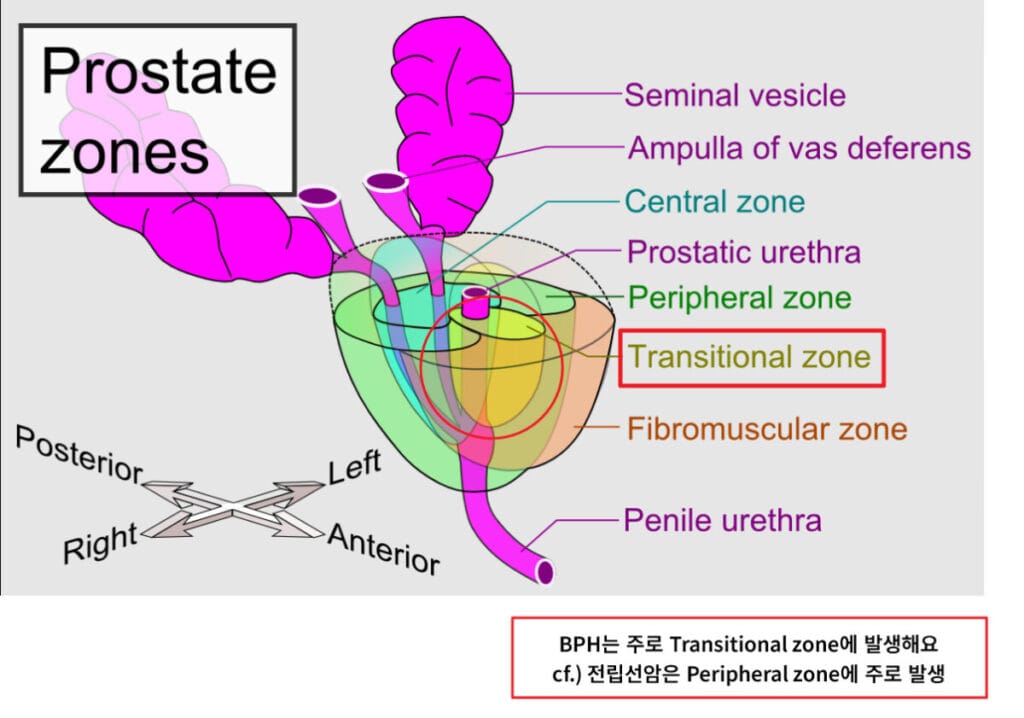

요도 주변의 전립선 Transitional Zone이 과형성되면서 배뇨 지연, 빈뇨, 약한 요줄기 등 하부요로증상을 유발합니다.

- Zones of the Prostate. Mikael Häggström, M.D. – Own work. References: “The Surgical Anatomy of the Prostate” in (2016) Prostate Cancer: Science and Clinical Practice, Academic Press, pp. 253–263 DOI: 10.1016/B978-0-12-800077-9.00029-3. ISBN: 9780128005927. Roberts MJ, Teloken P, Chambers SK. Prostate Cancer Detection. Endotext, at National Center for Biotechnology Information. Updated 2018 Jun 11